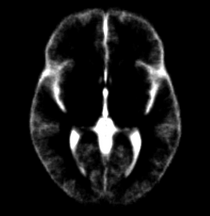

| + | | Template (T1) | ||

| + | | CSF | ||

| Template (T1) | CSF | Left GM1 (LTGM1) | Left WM1 (LTWM1) |